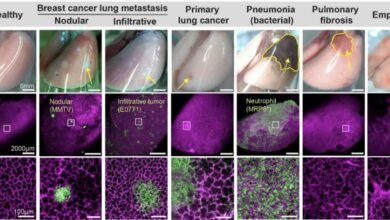

A tecnologia de ‘caixa torácica de cristal’ é pioneira em novas abordagens para a saúde pulmonar

A caixa torácica de cristal pode ser utilizada para estudar quase todas as doenças pulmonares que afetam os alvéolos (sacos…